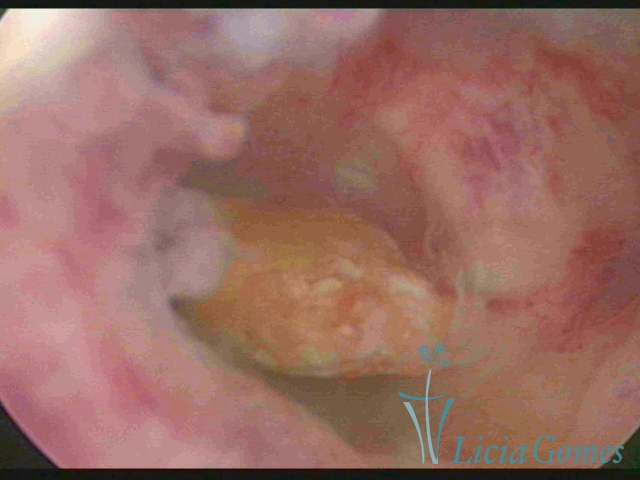

Intact egg cell debris in the uterine cavity

×